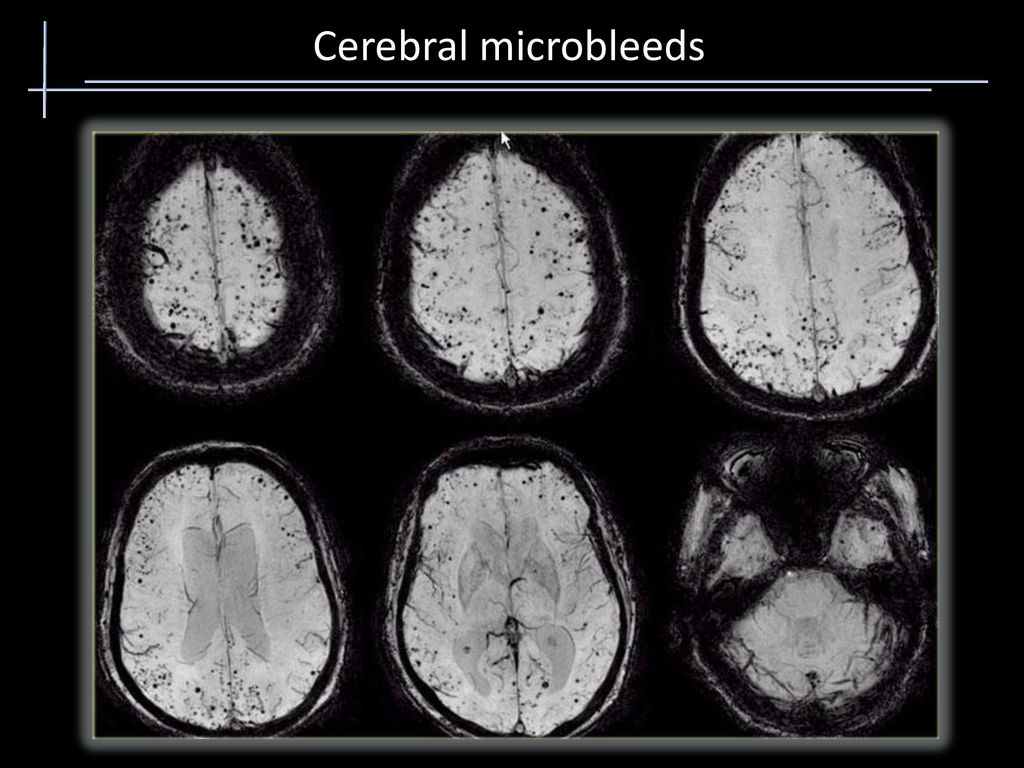

Fazekas grades. Амилоидная микроангиопатия. Церебральная микроангиопатия мрт. Дегенеративная микроангиопатия. Гипертензивная микроангиопатия мрт.

Fazekas grades. Амилоидная микроангиопатия. Церебральная микроангиопатия мрт. Дегенеративная микроангиопатия. Гипертензивная микроангиопатия мрт.